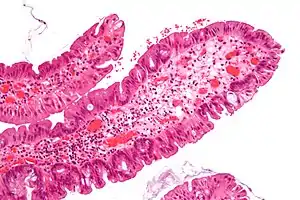

Micrograph of a villous adenoma. These polyps are considered to have a high risk of malignant transformation. H&E stain.